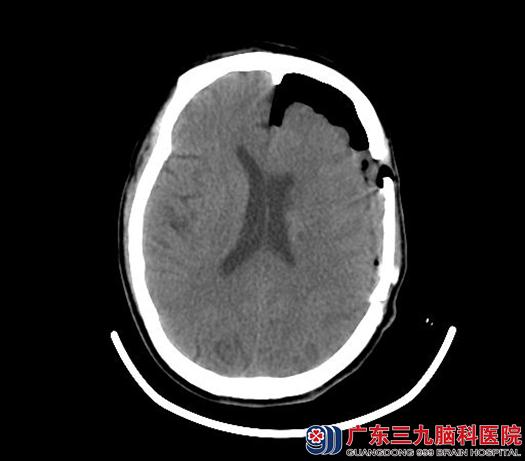

术后4小时CT